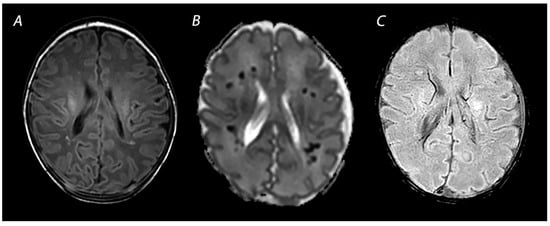

3.3. Susceptibility Weighted Imaging

- Kitamura, G.; Kido, D.; Wycliffe, N.; Jacobson, J.P.; Oyoyo, U.; Ashwal, S. Hypoxic-ischemic injury: Utility of susceptibility-weighted imaging. Pediatr. Neurol. 2011, 45, 220–224. [Google Scholar] [CrossRef]

- Messina, S.A.; Poretti, A.; Tekes, A.; Robertson, C.; Johnston, M.V.; Huisman, T.A. Early predictive value of susceptibility weighted imaging (SWI) in pediatric hypoxic-ischemic injury. J. Neuroimaging 2014, 24, 528–530. [Google Scholar] [CrossRef]